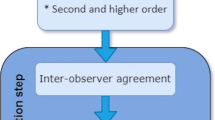

Thirty-five volunteers (30 (SD 11) yrs.) with and without chronic back pain spent 20 min lying in a relaxed unloaded supine position, followed by 20 min loaded in compression, and then 20 min with traction applied. T2-weighted MR images were acquired during the last 5 min of each loading condition. Custom image analysis software was used to segment discs from adjacent tissues semi-automatically and segment each disc into the nucleus, anterior and posterior annulus automatically. A grey-level, co-occurrence matrix with one to four pixels offset in four directions (0°, 45°, 90° and 135°) was then constructed (320 feature/tissue). The Random Forest Algorithm was used to select the most promising classifiers. Linear mixed-effect models and Cohen’s d compared loading conditions.